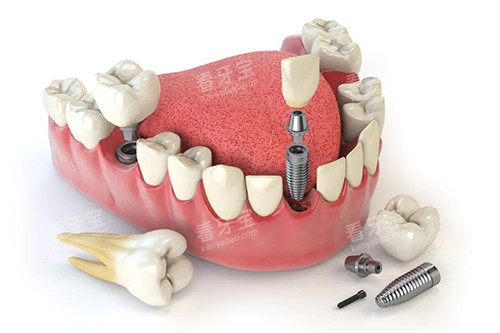

在种植牙方面,医生会根据患者的口腔状况、骨质条件等因素,选择合适的种植体和种植方案。

同时,在种植过程中,采用新型的种植技术,确保种植的可行性和稳定性。